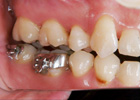

虫歯、歯周病の問題を解決した上で矯正治療を行い、

矯正治療終了後、矯正治療では不可能な微妙なかみ合わせの調整をして、

全身とかみ合わせのバランスを整えます。(→かみ合わせ治療) |

・健康な歯

・健康な歯肉(歯周組織)

・全身とのバランスがとれたかみ合わせ(→かみ合わせ治療) |

| この3つがすべてそろうことで矯正治療は成立します。 |